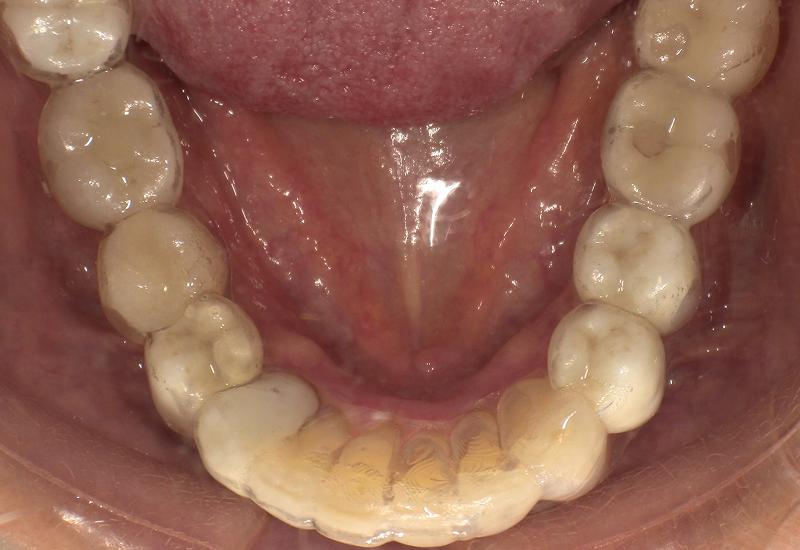

症例① シェイプメモリーアライナーによる下顎の前歯の矯正

治療期間 7ヶ月

治療時の年齢/性別 68歳 / 女性

かかった治療費 440,000円

治療方法 シェイプメモリーアライナー

注意点・詳細

• 根管治療をしてある歯はなるべく動かさない

• 下の前歯の歯の形を少しだけ小さく整えた